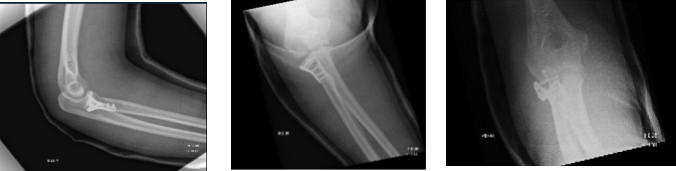

The patient undergo X-ray every week to monitor the progress of the elbow radial fracture. Postsurgical changes at the radial head are noted with satisfactory position of the hardware. In the second week, can notice the Stable postsurgical changes involving the proximal radius.

Third week post saw the repair of a complex fracture of the proximal radius in a good position fixed with plate and screws. After a month, early healing of the surgically treated comminuted radial head fracture is noted.

We have decided to do formal physical therapy as well as a home exercise program for rehabilitation of the knee. The patient regularly followed an office visit every 3-4 weeks. Patient did well after the surgery and continued physical therapy.